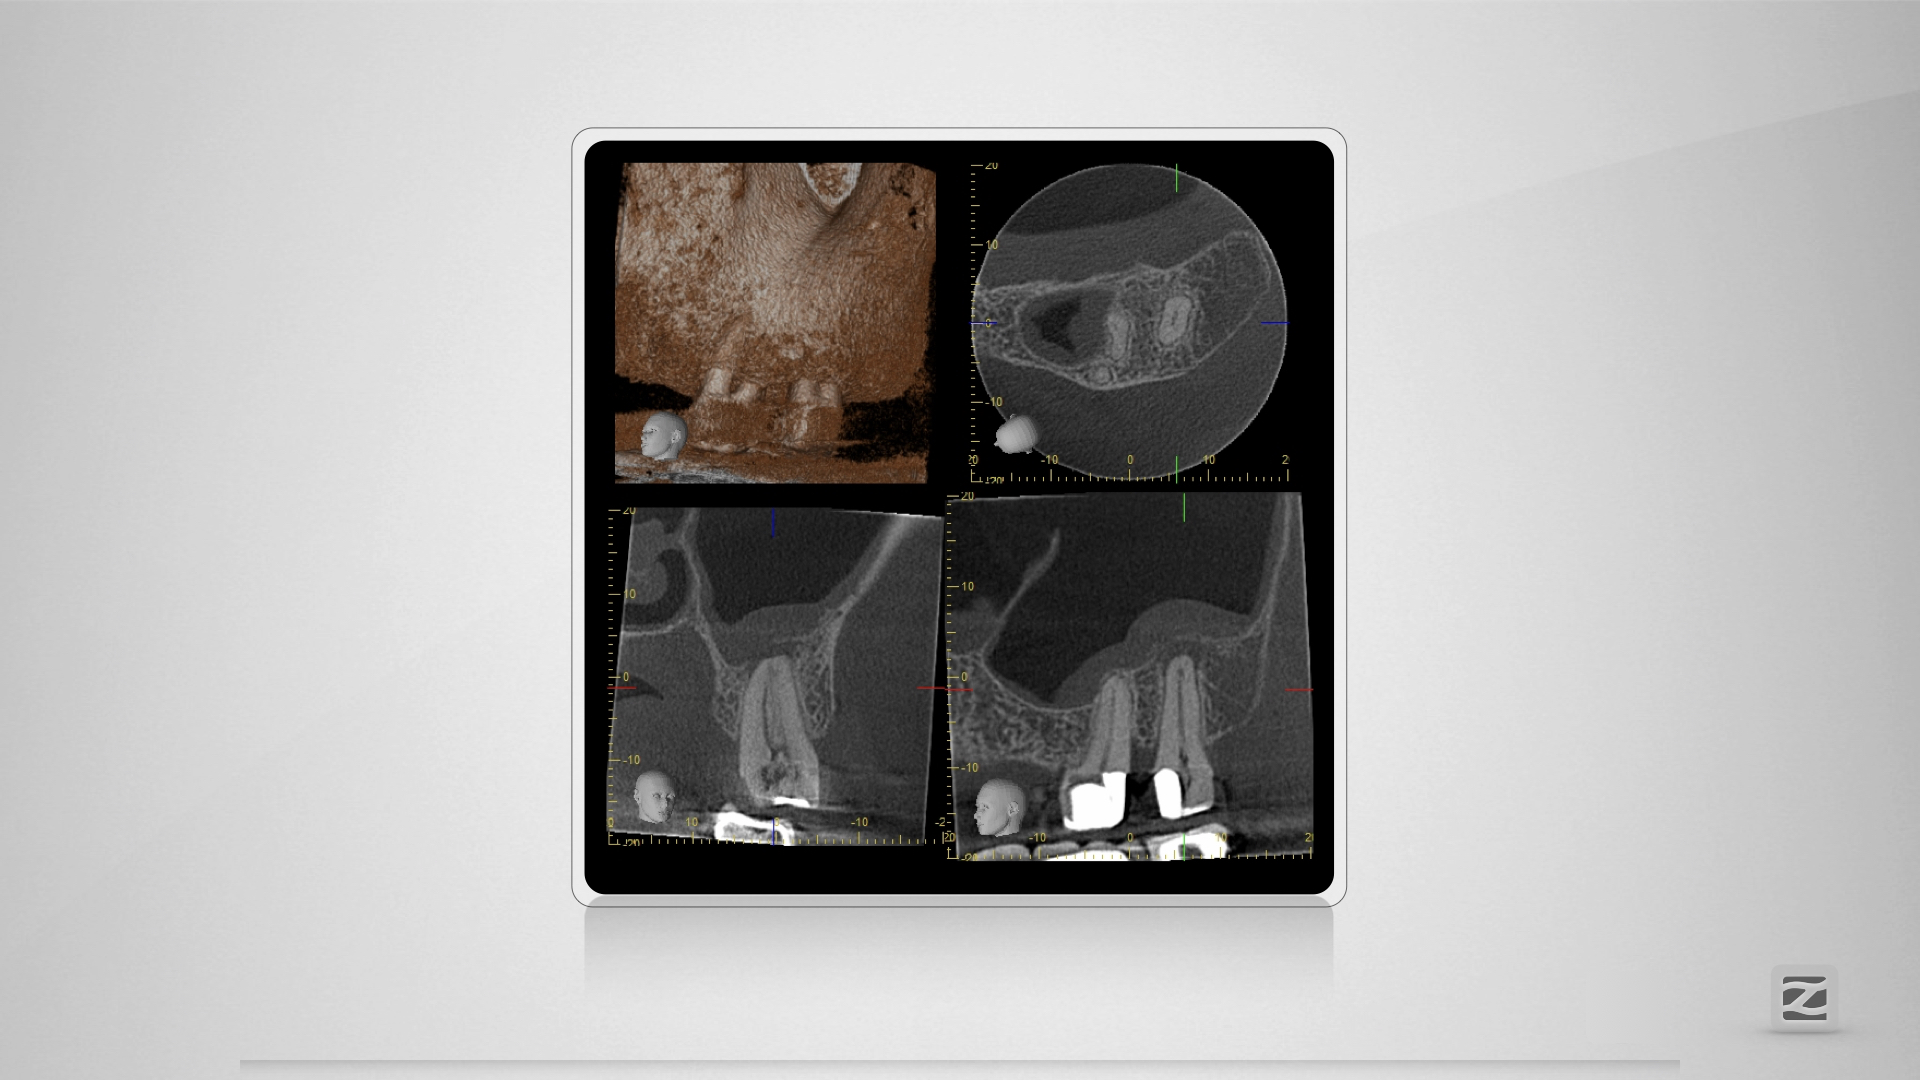

Großer Dentikel, tiefer Split.